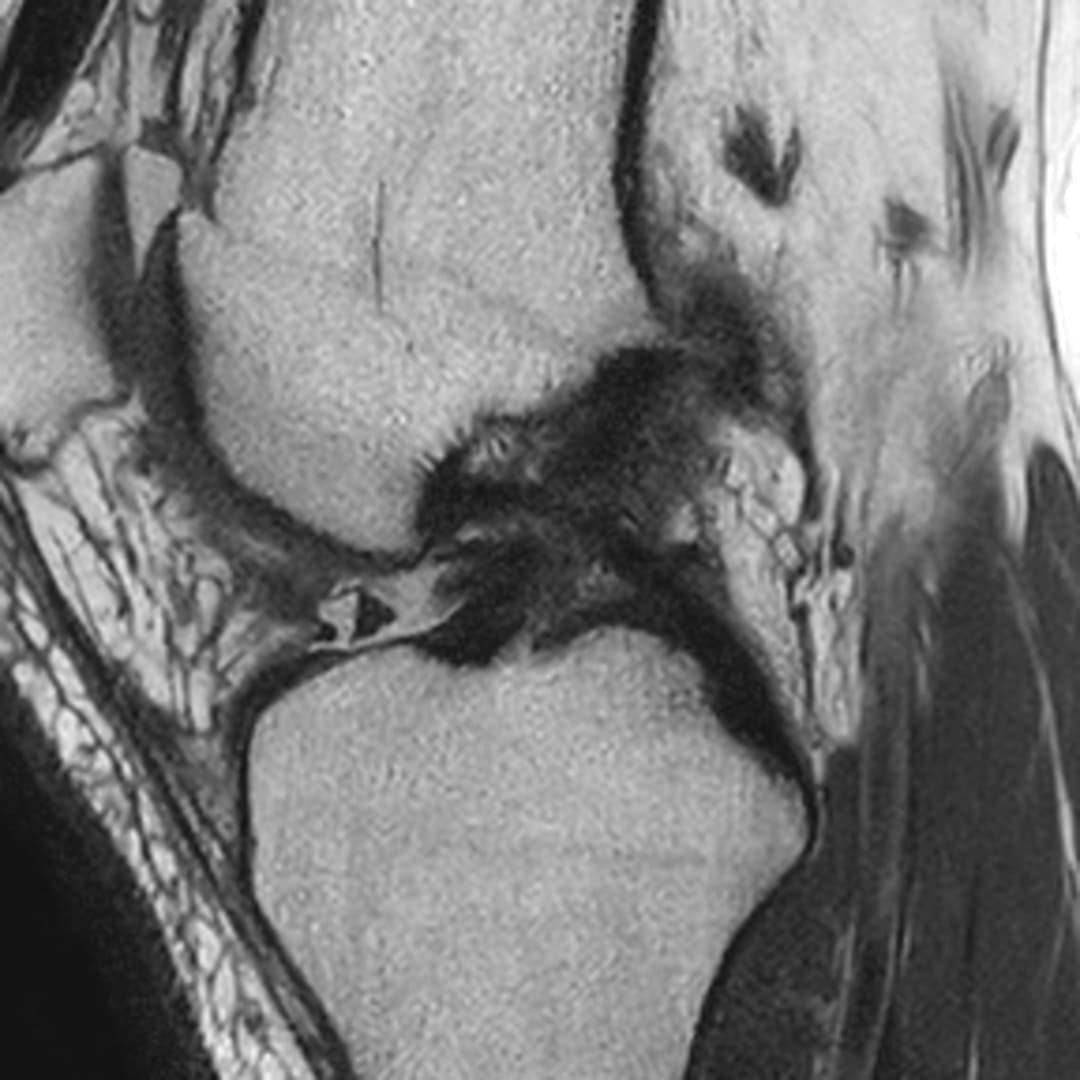

Fissure de grade 3 du segment moyen du ménisque médial.